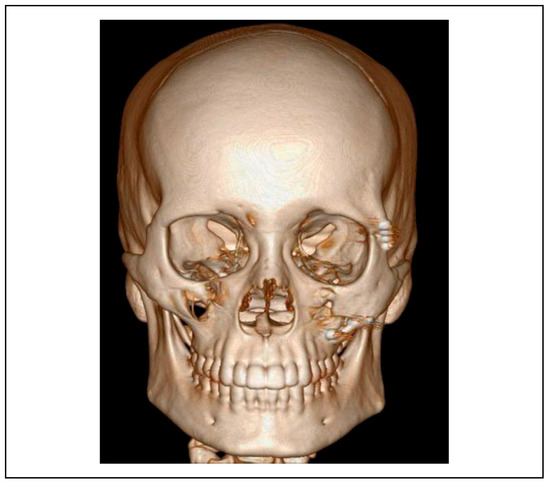

The protocol for this study included imaging in the form of a preoperative and postoperative 3D computed tomography scan with reconstruction of the maxilla and mandible to interpret the diagnosis for all subjects. A standard CT scanner (GE ADW 4.5 workstation) was used with a 0.60 mm slicing mechanism depicting axial, coronal and sagittal sections [4] (Figure 1 and Figure 2). The inter-fracture distance of the fractured infraorbital rim were measured in 3 dimensions (antero-posterior, medio-lateral and supero-inferior) and compared pre and postoperatively. All subjects of the study group underwent an ultrasonographic examination intraoperatively using a mobile ultrasound machine (SONOSITE S-ICU) with a standard transducer (linear probe—L14-5) in variable frequencies ranging from 6 to 10 MHz. Images were depicted with a 70% gain and 60% depth of focus.

Figure 1.

Preoperative CT scan—3D.